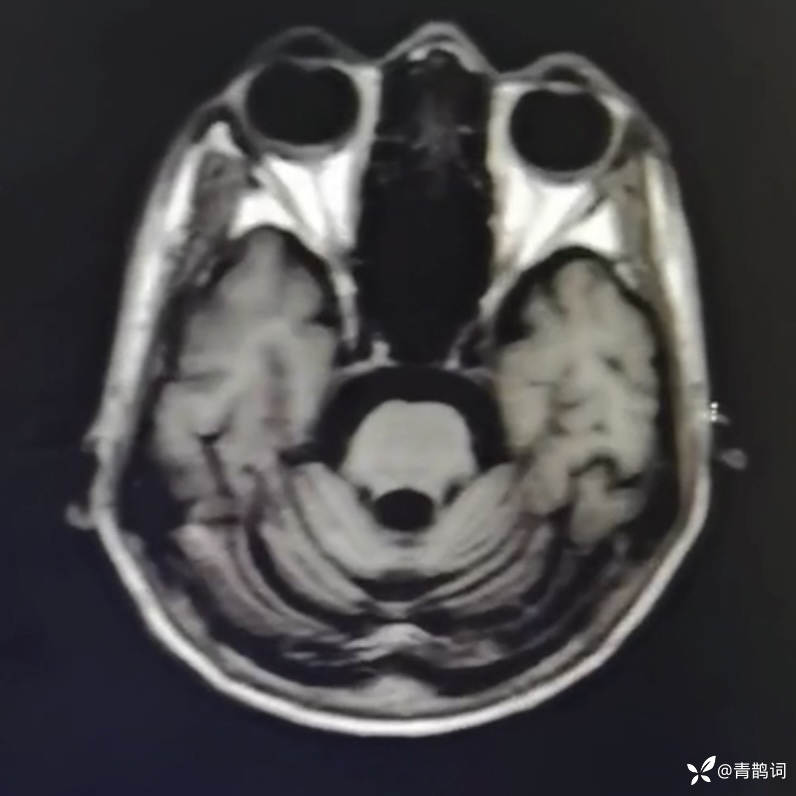

乐痴于医等 2人推荐简要病史:42岁男性,记忆力下降及听力下降一年余。既往体健,否认前驱感染病史。否认家族史。三个月前就诊于当地医院,自述腰穿脑脊液乳酸增高。现就诊于我院,查体记忆力下降,计算力下降,定时定向差,吟诗样语言。完善磁共振如下:

T2: